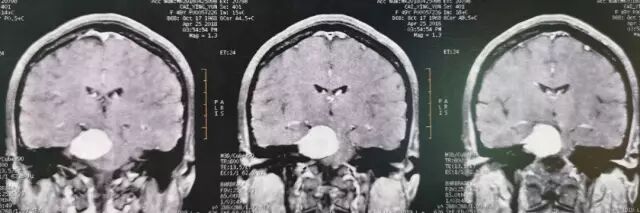

查体:神清语利,双瞳等,光反应灵敏,右侧面部浅感觉减退,行走不稳,四肢肌力基本正常。核磁共振检查见右侧岩斜区肿瘤,考虑岩斜脑膜瘤。

肿瘤强化明显,部分侵入海绵窦。

术后MRI增强核磁扫描